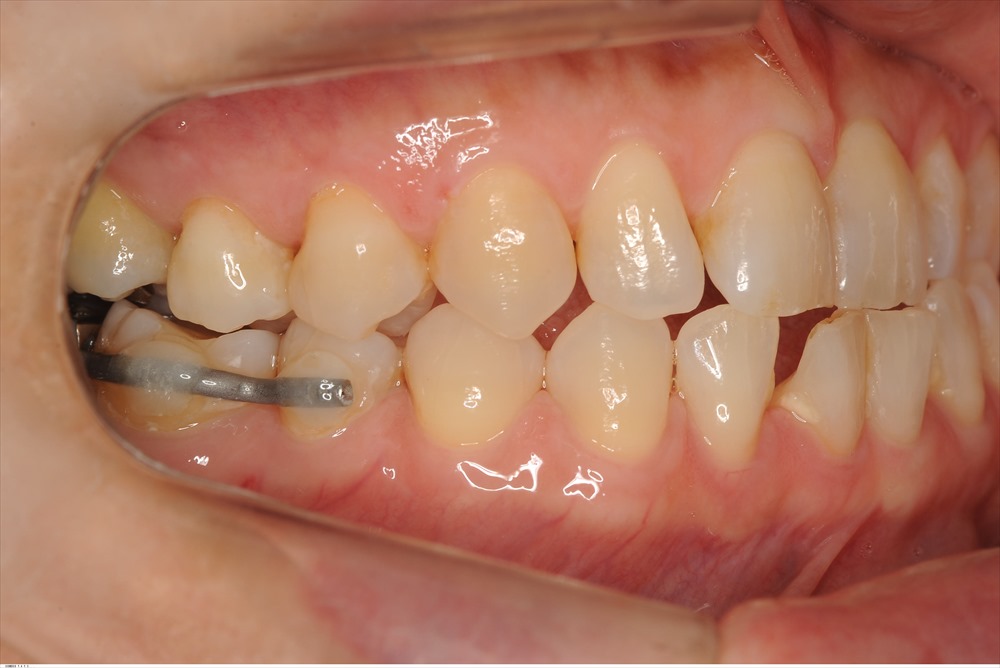

術後1年でここまで回復

勿論、歯茎も切っていません、再生材料も一切使用しておりません。